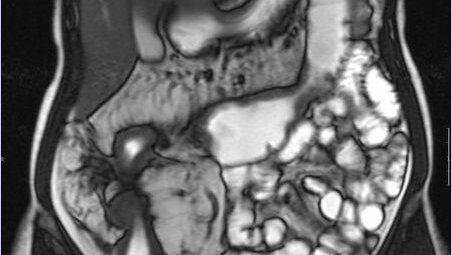

Гидро-МРТ кишечника – это неинвазивная и высокоинформативная методика диагностики тонкого кишечника. Такая магнитно-резонансная томография требует применения высокопольного томографа с мощностью магнита не менее 1,5 Тесла и специального протокола - гидроусиления...